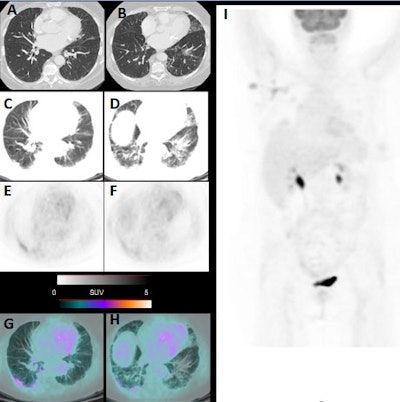

Images include high-resolution thoracic CT with no sign of pneumonia (A, B). PET/CT performed one week later, showing bilateral pneumonia with ground-glass opacities at CT (C, D), PET (E, F), and PET/CT fused images (G, H) with SUVmax of five. Maximum intensity projection (I) shows axillary nodal lesion as FDG positive. Images courtesy of Journal of Nuclear Medicine.To ensure the six cases of incidental pneumonia in March 2020 were not an aberration, the researchers compared their caseload from the same eight days of March 2019 and found only two cases (2.5%) of incidental pneumonia among 80 PET/CT studies.

Following completion of the scans, six patients (9%) showed signs of pneumonia on CT and FDG avidity in all areas of pneumonia, which made these patients suspicious for COVID-19. The six patients included four women, between 55 and 65 years old, and two men, ages 65 and 77, respectively. When physicians followed up with reverse transcription polymerase chain reaction (RT-PCR) tests, five patients (83%) were confirmed to have COVID-19.